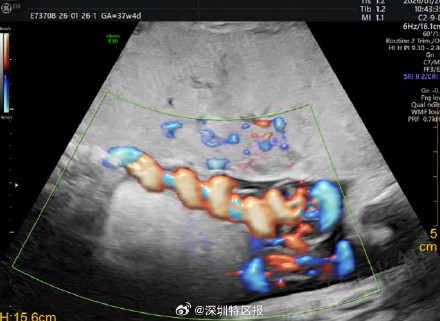

近日,广东深圳。怀孕37周的王女士常规产检时,超声团队发现胎儿脐带严重扭转,血流近乎中断,胎儿已宫内缺氧!医院立即启动绿色通道,从诊断到推入手术室仅用28分钟。术中可见脐带已扭成骇人“麻花”,与超声诊断完全吻合。女婴顺利娩出,宝宝的生命评分(Apgar)完全正常。为深圳医护点赞! @深圳晚报